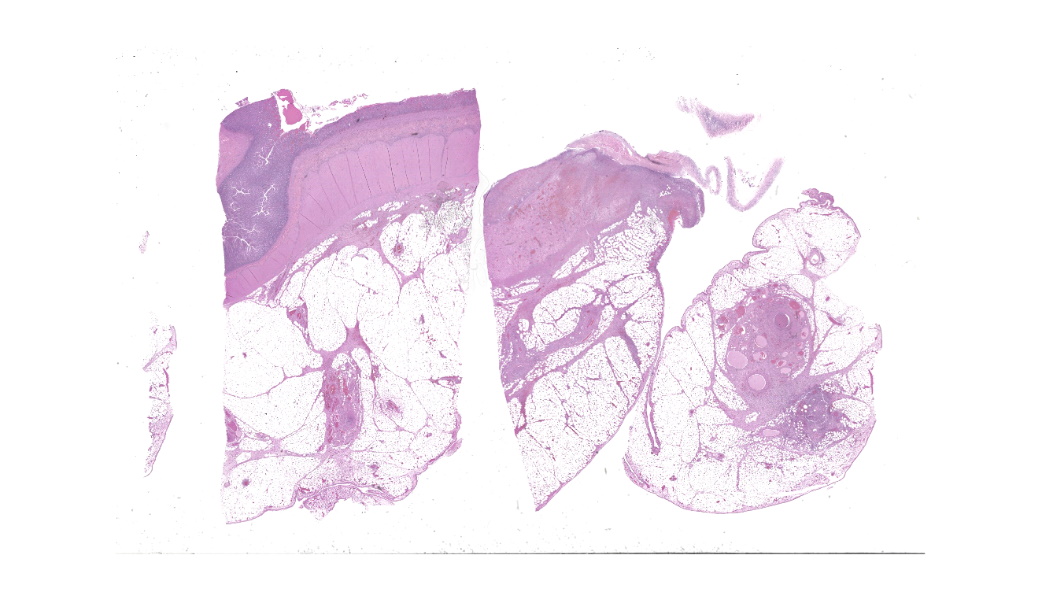

Findings are very similar in all cases that were submitted to the diagnostic laboratory.In all samples from the grossly discolored and swollen segment there was transmural necrosis of the intestine with extensive hemorrhage extending into the mesenteric fat. In the adjacent viable intestine there was eosinophilic infiltration of variable intensity. There was multifocal necrosis of mesenteric fat and, in some sections, diffuse eosinophilic infiltration. Large vessels were dilated and many contained thrombi.

Within the media of medium to small sized arteries there were sections (not present in all slides due to the small size of the parasite – but see photomicrographs) of a nematode larva, approximately 100-200 µm in diameter with lateral allae and central digestive tract. These features are consistent with a spirurid of which Spirocerca is the most likely in our region. Foci of necrosis with hemorrhage were observed in the media of some arteries, where no larvae were identified.

Acute transmural necrotizing eosinophilic enteritis and eosinophilic peritonitis with arterial mesenteric thrombi and rare intralesional nematode larvae (spirurid)Contributor's Comment: